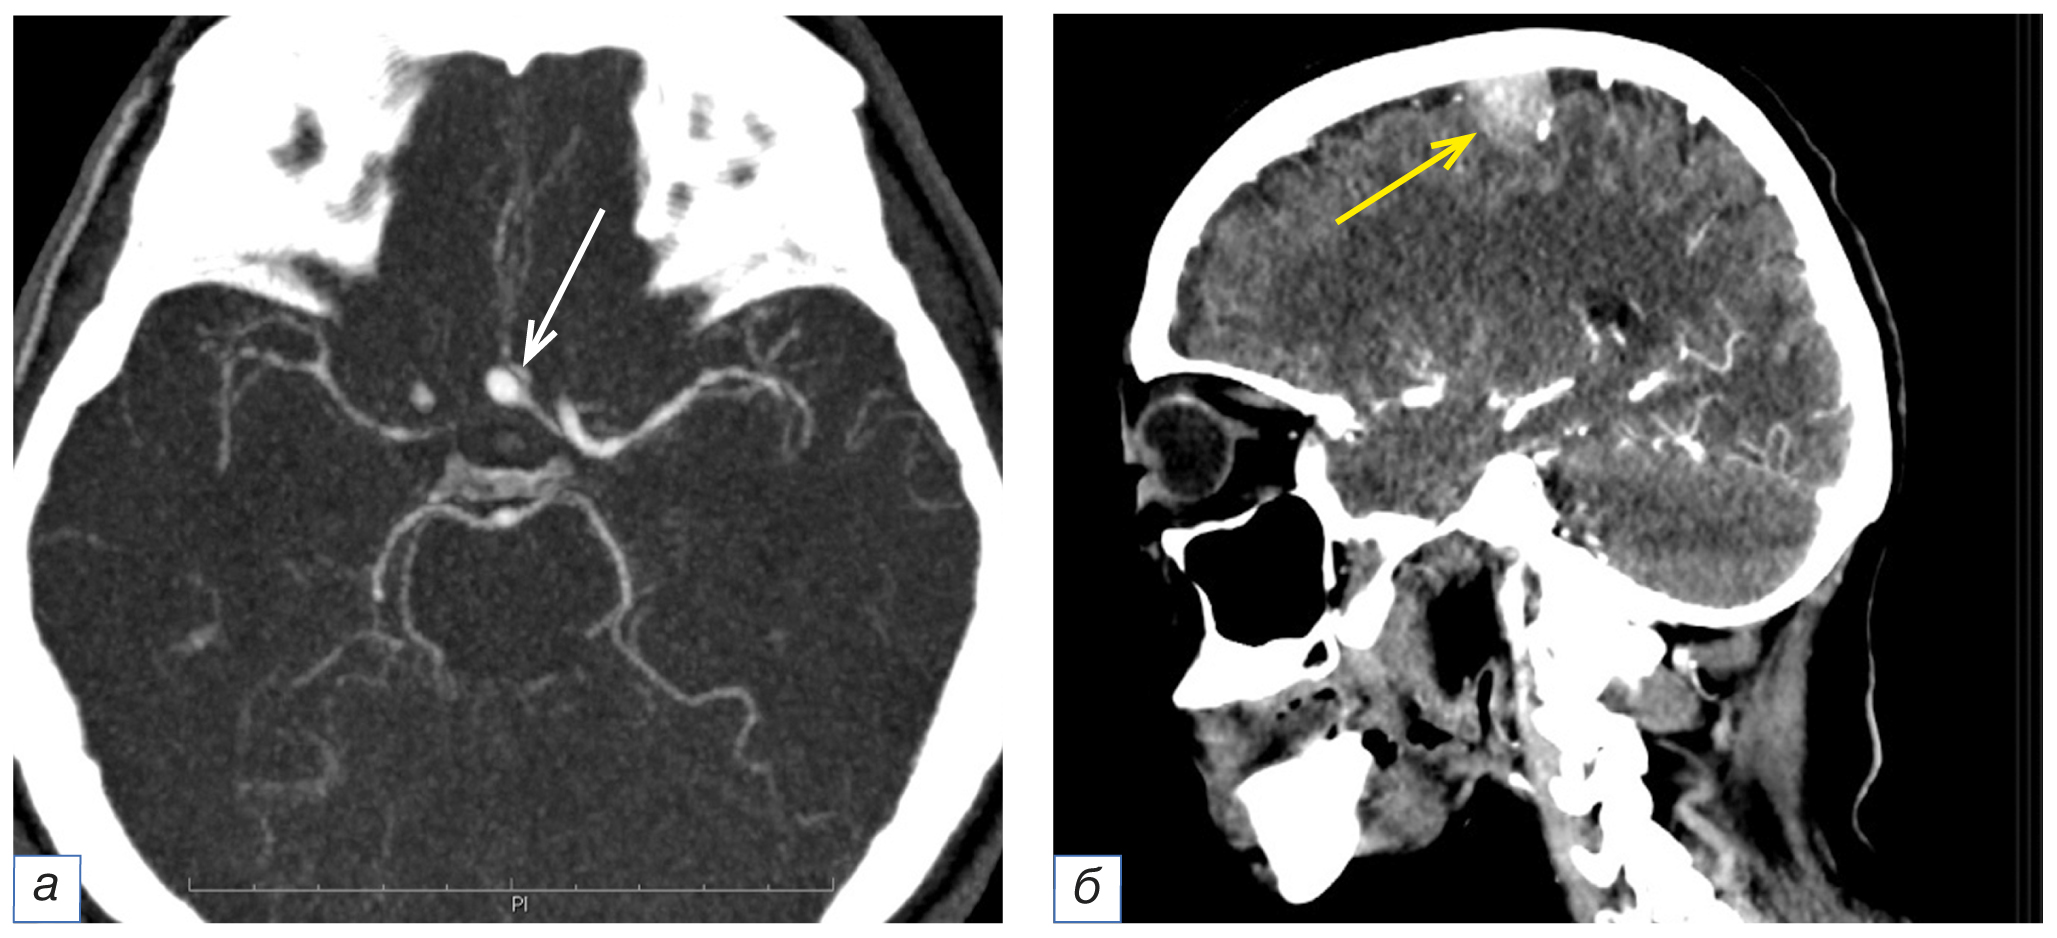

Интракраниально расположенные патологические находки не были описаны в 5 (8,1%) случаях. К ним относились аневризмы интракраниальных артерий головного мозга (n=2), располагавшиеся в области сегмента А1 передней мозговой артерии и бифуркации сегмента М1 средней мозговой артерии, а также внемозговое образование в области левого мостомозжечкового угла (n=1), конвекситально расположенное внемозговое образование в правой теменной области (n=1) и интраселлярно расположенное образование (n=1) (рис. 3). Также в 5 (8,1%) случаях в заключении отсутствовало упоминание о наличии изменений в височных костях с односторонней локализацией воспалительных изменений в виде патологического субстрата в ячейках сосцевидного отростка и барабанной полости.

Рис. 3. Фрагменты компьютерных томограмм области головы и шеи в аксиальной (а) и сагиттальной (б) плоскостях. У пациента в возрасте 55 лет с диагнозом рака гортани сТ2N0M0 определяется мешотчатая аневризма сегмента А1 левой передней мозговой артерии диаметром 5 мм (а, белая стрелка). У пациентки в возрасте 76 лет с диагнозом рака гортани Т4N1M0 в правой теменной области отмечается округлой формы гиперваскулярное образование с чёткими ровными контурами, широким основанием, прилежащее к внутренней поверхности правой теменной кости (б, жёлтая стрелка).

Fig. 3. Computed tomograms of the head and neck, axial (а) and sagittal (б) planes. A 55-year-old patient with laryngeal cancer cT2N0M0 has a saccular aneurysm of the left anterior cerebral artery A1 segment, diameter 5 mm (а, white arrow). A 76-year-old patient with laryngeal cancer T4N1M0 in the right parietal region has a round-shaped hypervascular formation with clear, even contours, a wide base adjacent to the inner surface of the right parietal bone (б, yellow arrow).